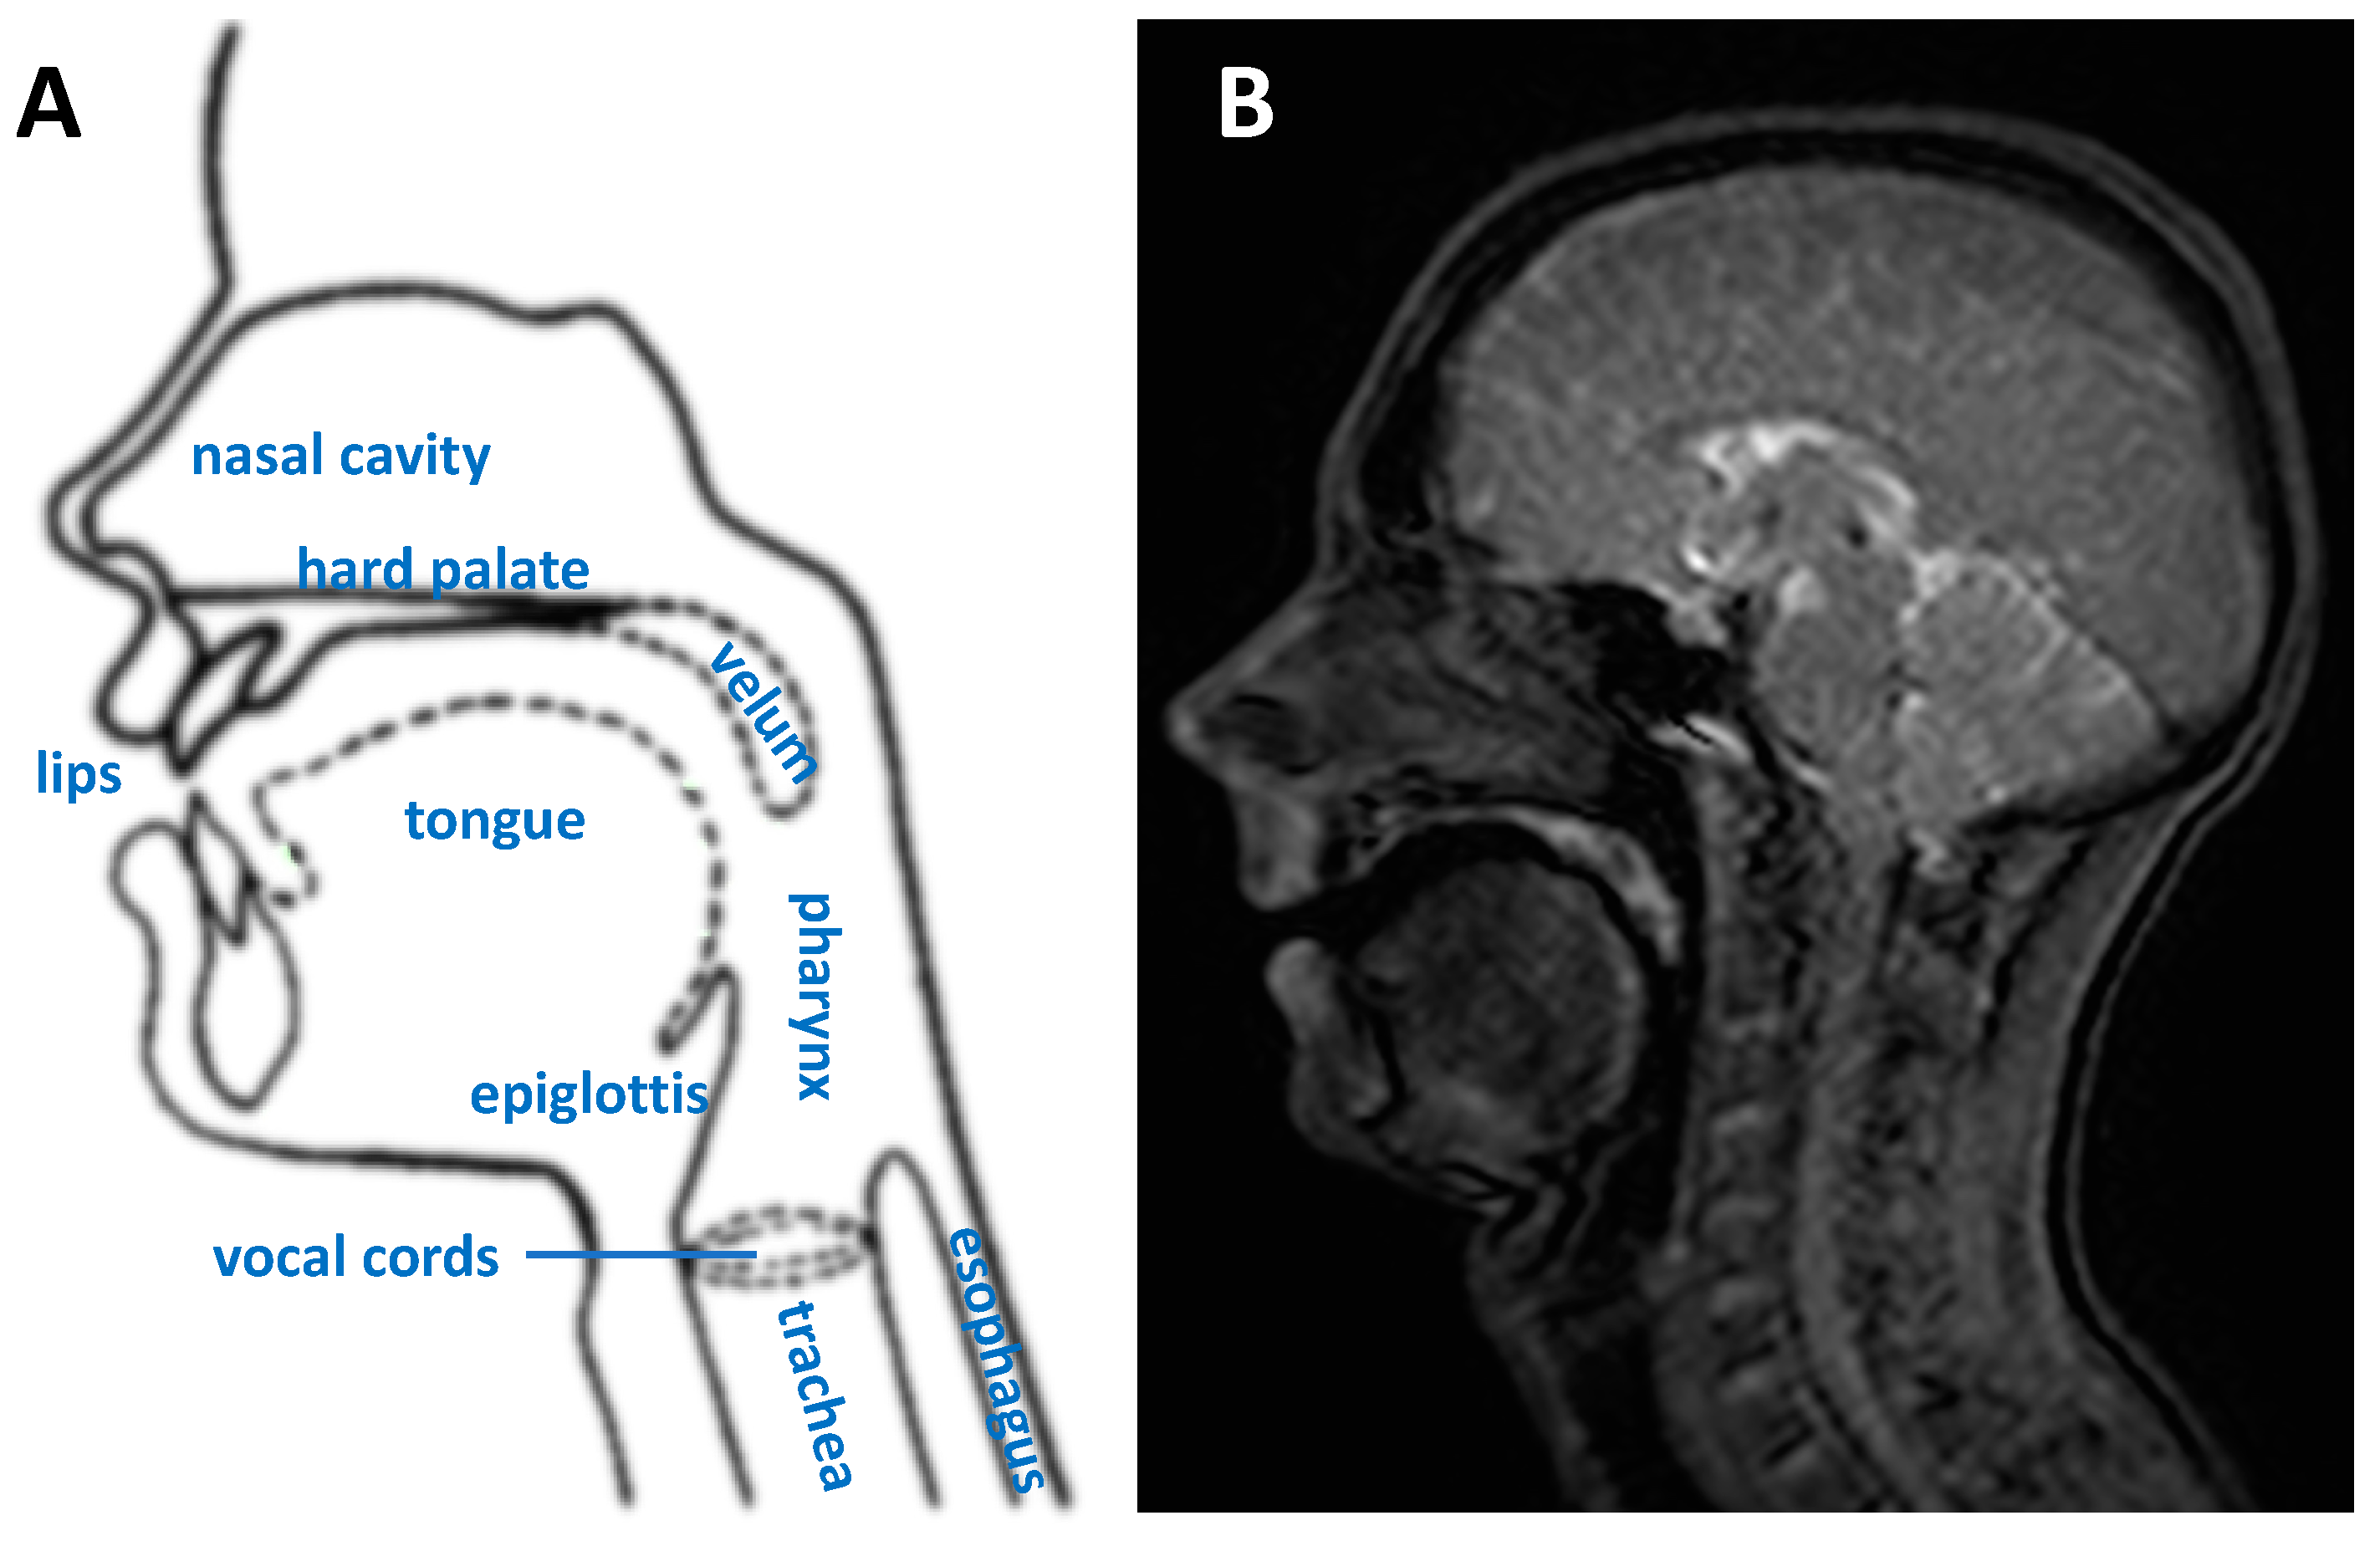

The upper vocal tract is an anatomical region covering the neck from the vocal cords to the mouth and nasal cavity (Figure 1). The production of speech is a complex process that involves numerous organs, referred to as articulators, including the lips, teeth and jaw, tongue, soft palate or velum, nasal cavity, the pharynx and vocal cords (or folds). Air from the lungs is forced through the vocal folds; their vibration produces a frequency and harmonics that can be controlled by the vocal cords. The other articulators form a network of connected resonant cavities that can be modified in shape and size allowing complex sounds to be formed [1,2]. At the back of the tongue lies the epiglottis, a flap that is open during respiration and speech and that closes to force food and fluids along the esophagus while preventing it from entering the trachea (Figure 1).

Figure 1.

(A) A mid-sagittal diagram of the upper vocal tract highlighting the main speech organs or articulators. (B) A corresponding typical frame from a dynamic MRI scan during speech.